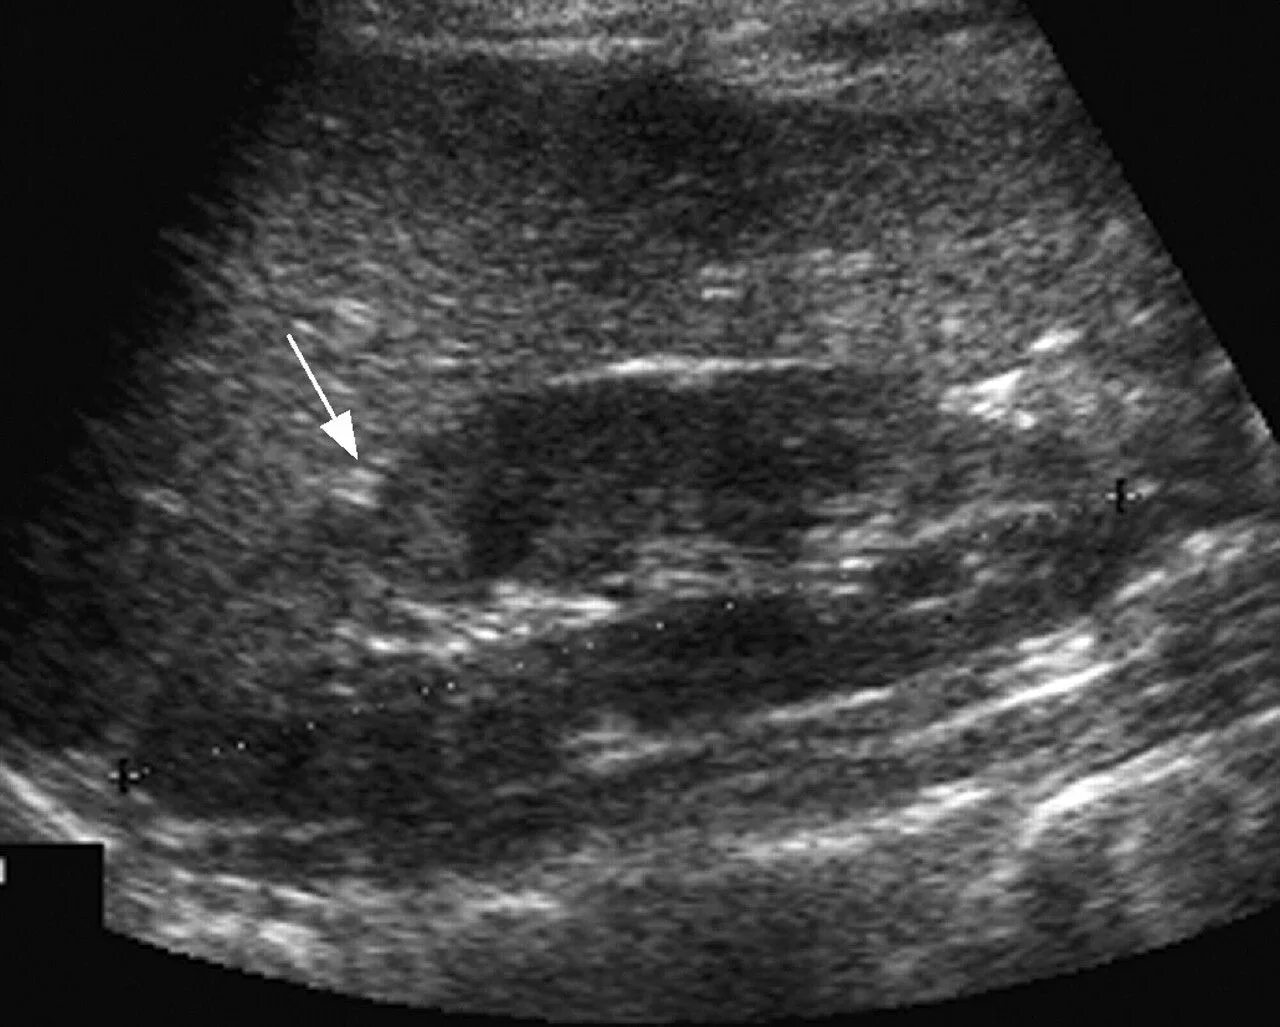

Нефросклероз почек на узи что это такое